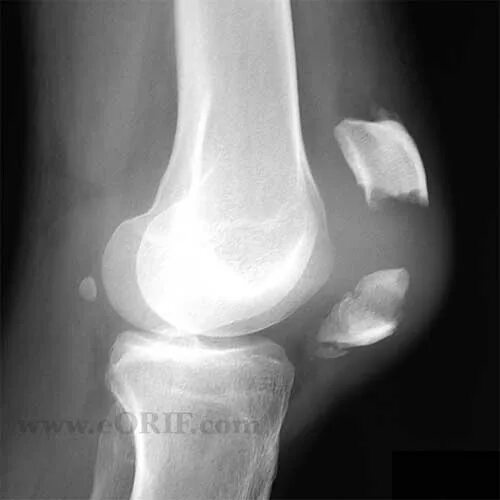

Смещение колена